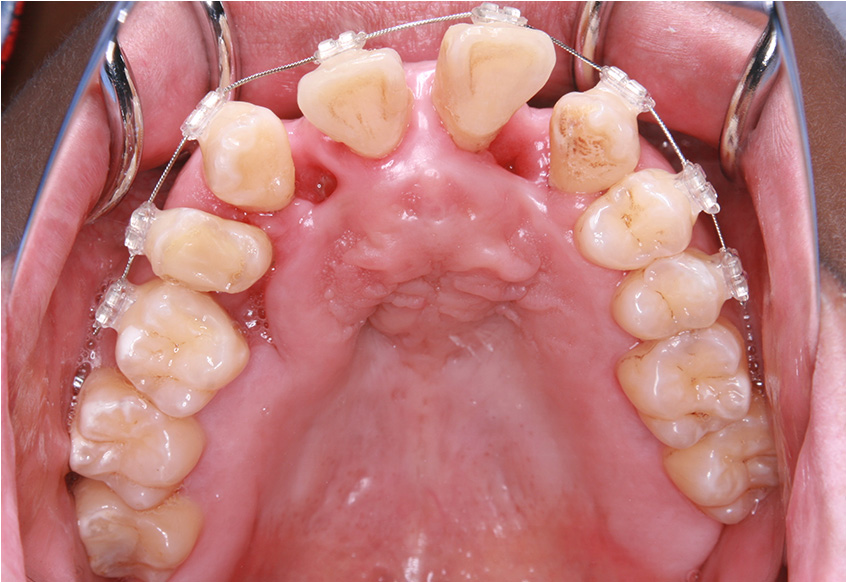

最初のお口の中 ワイヤー装着して治療を開始

-

治療開始後3ヵ月経過すると、前歯の隙間や全体の乱れが減ってきました。口笛が吹けるようになったとのことです。

最初のお口の中 治療開始3ヵ月後